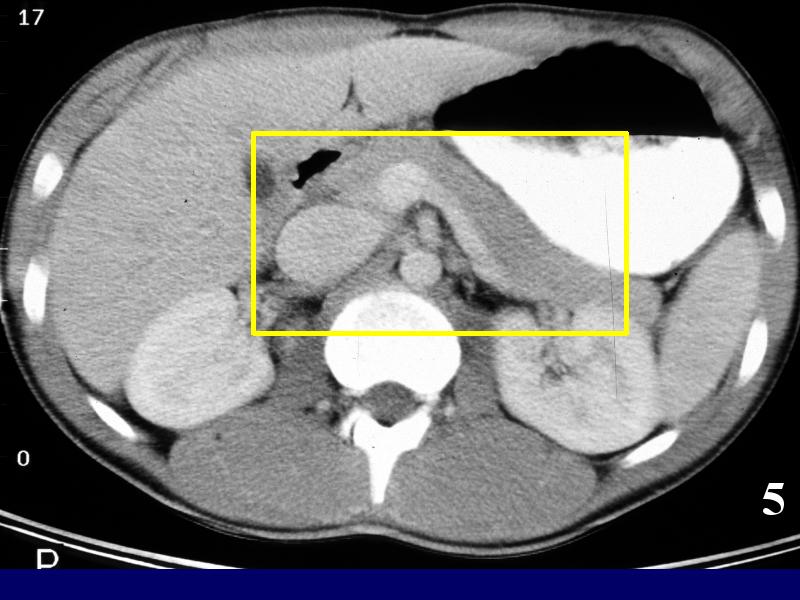

MS 190 CT 16